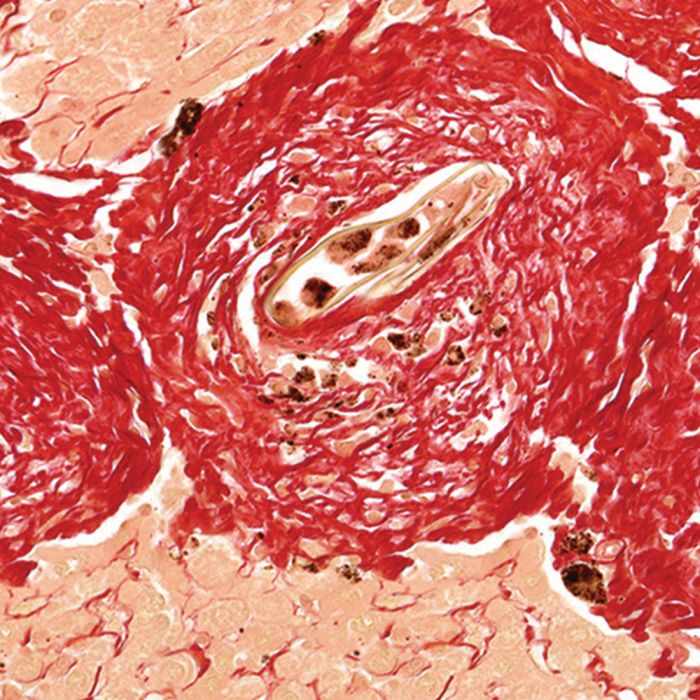

Collagen Type I and III Staining

Our Picrosirius Red Stain binds specifically to collagen fibrils of varying diameter that is used to distinguish collagen Type I from Type III. Picrosirius Red Stain will quantify the amount of collagen in a given area of myocardial tissue. (i.e. the collagen area fraction)

Collagenous structures of the mandible stain brilliant red. Unlike sections stained with hematoxylin and eosin alone, dentinal tubules, Sharpey's fibers and other structures can be seen clearly after using Picrosirius Red Stain procedure. Under polarized light, collagen fibers can be specifically identified and their orientation determined.